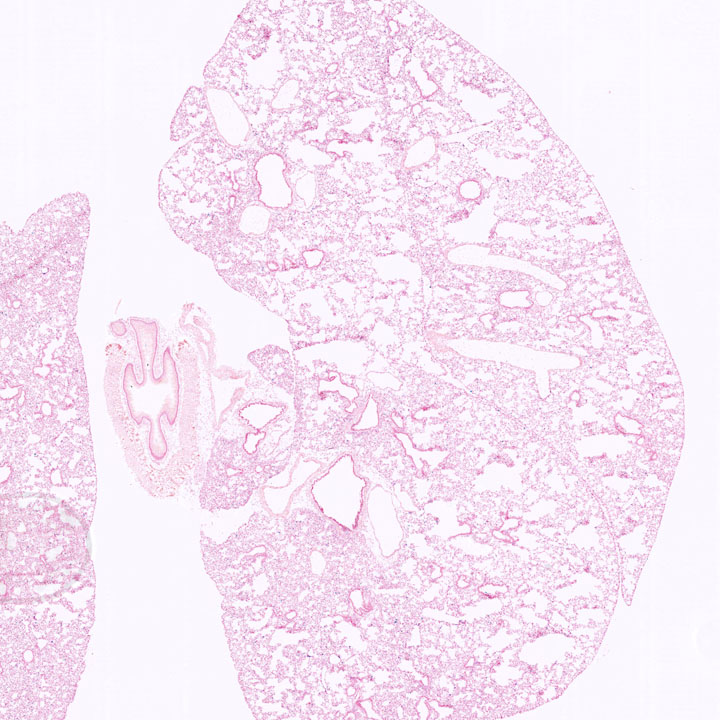

Respiratory System

Images

Drag images to compare to others or to data in the table below. Drag corners to resize images for more detail.

Recombinase Activity